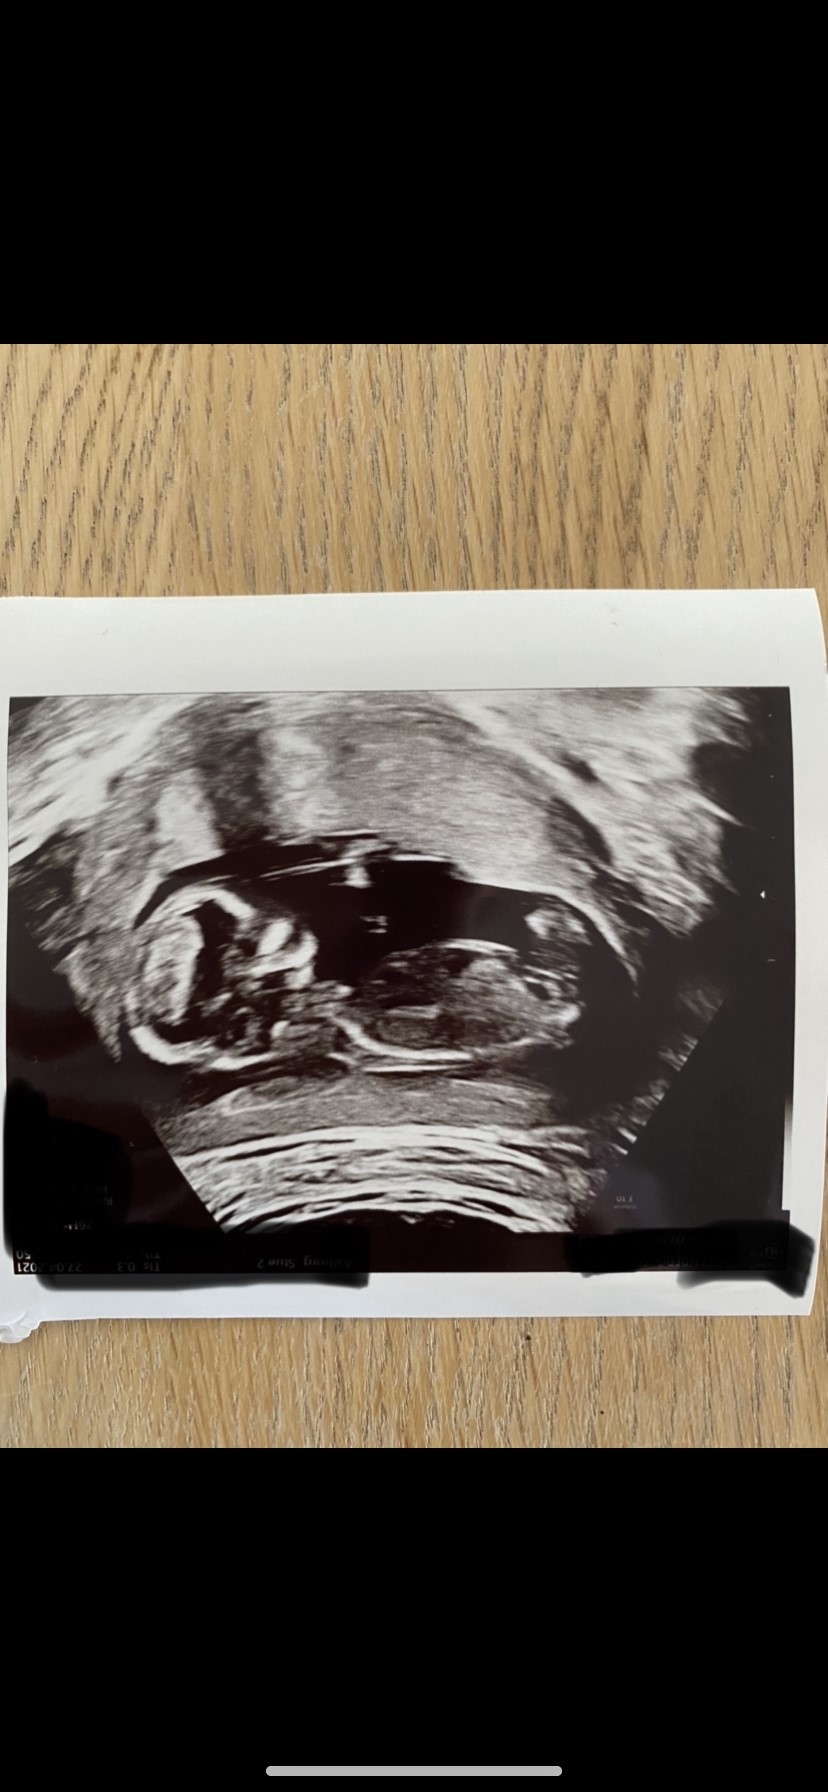

Nogle der måske kan se kønnet her? Bebsen var desværre lidt stædig og ville ikke heeeelt ses ordentlig til nakkefold i dag, men måske man alligevel kan se det?

Vedhæftede fotos (klik for at se i fuld størrelse)

Jeg gætter på dreng ud fra skull theory

Mit bud er også dreng